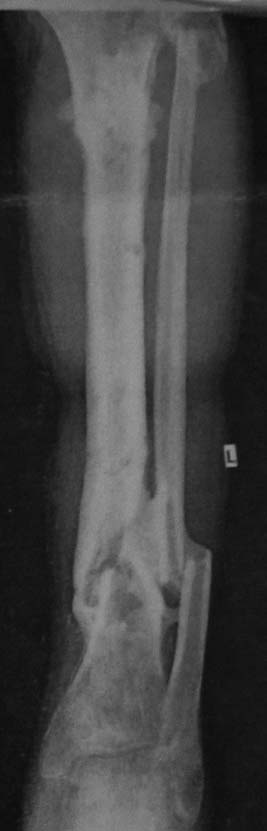

Хронический остеомиелит н/3 б/берцовой кости+атрофичный ложный сустав в/3 б/берцовой кости

Мужчина, 50 лет. Травма в результате ДТП в сентябре 2012 года. Сочетанная травма. ЗЧМТ. Ушиб головного мозга. З/переломы 5-8 ребер справа, пневмогемоторакс. З/двойной перелом обеих костей правой голени

Проводилось оперативное лечение – БИОС б/берцовой кости штифтом, затем КДО аппаратом Илизарова (открылись свищевые ходы на уровне н/3 голени). Впоследствии аппарат Илизарова был заменен на ортез. Больной в январе 2013 года был выписан на амб. долечивание. Через 5 месяцев вновь открылись свищевые ходы. В условиях стационара неоднократно проводилась антибиотикотерапия (достигнуты нестойкие ремиссии), фистулография. На данный момент имеется атрофичный ложный сустав в/3 б/берцовой кости, остеомиелит н/3 б/берцовой кости, свищевая форма. Больной передвигается при помощи костылей с дозированной нагрузкой на ногу в ортезе. На уровне ложного сустава в/3 б/берцовой кости определяется легкая подвижность, в н/3 б/берцовой кости подвижности нет.